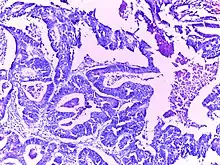

![]() | Adenocarcinoma stomach | Micrograph of carcinoma stomach. The glands are seen infiltrating the muscle layer. The neoplastic cells are arranged in cords and in glandular pattern. The cells show dysplastic features. Signet rings with nucleus pushed to the periphery are seen in some types of adenocarcinoma. | Category: Histopathology of adenocarcinoma stomach | Adenocarcinoma of stomach |